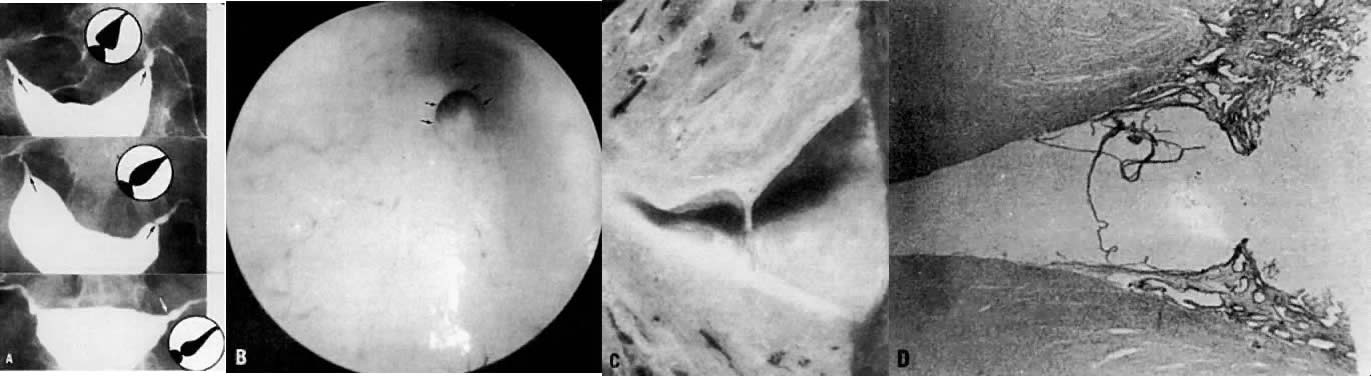

The HSG should be fluoroscopically controlled under image intensification with water-soluble contrast material. Small increments of the contrast material are injected. The end points are either tubal fill and spill, or increasing abdominal pain in the absence of tubal filling. The drainage film is essential to ascertain the presence of spill or localization, and to evaluate rugae in the distally obstructed tube (Fig. 1). The association of salpingitis isthmica nodosa with a hydrosalpinx in the same oviduct represents a contraindication to further attempts at tubal reconstruction. Laparoscopy is employed for diagnostic confirmation and possible therapeutic procedures. Other endoscopic techniques that have become a part of the evaluation of the fallopian tube include salpingoscopy3 and falloposcopy,4 the latter utilizing a linear everting catheter.

Fig. 1. A. This ampullary segment shows dark lines (arrows) denoting rugae. B. Drainage film reveals good dispersion of contrast material. C. Drainage film shows localization of contrast material bilaterally. Irregular borders (arrows) denote severe damage to the endosalpinx.